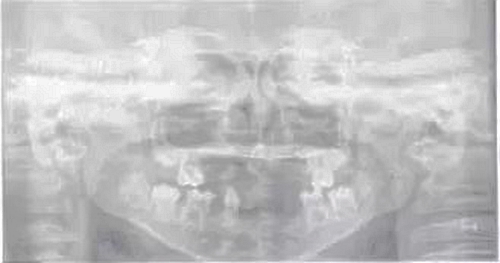

圖1患兒曲面斷層片

頜面斷層檢查:運(yùn)用數(shù)字放射影像技術(shù)評(píng)估患者缺牙區(qū)牙槽嵴和下頜骨解剖狀況,追問(wèn)病史,患兒家長(zhǎng)否認(rèn)近親結(jié)婚史及家族史。診斷為:(1)小兒軟骨外胚層發(fā)育不全綜合征;(2)牙列缺損。就診后,行全面口腔檢查,取模,制作研究模型。經(jīng)與患者協(xié)商溝通,采用覆蓋義齒修復(fù)。